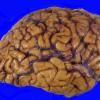

Subcortical Arteriosclerotic Encephalopathy (4)